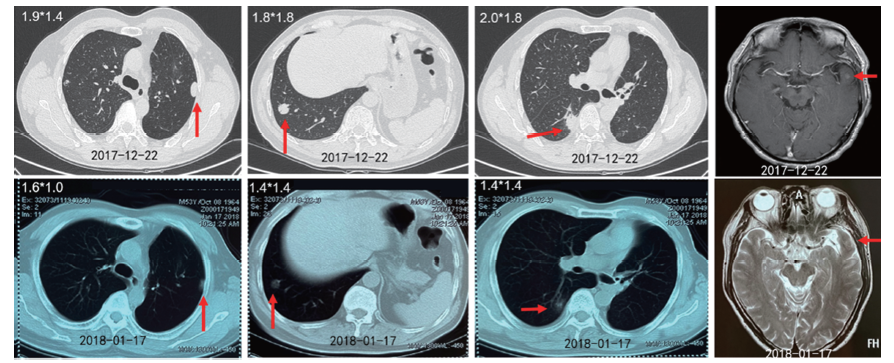

按照MTD讨论意见, 虽然已发现颅内转移结节, 但肿瘤生长非常缓慢, 转移病灶不足1 cm, 遂予继续观察。2017-10-12复查CT及头颅MR提示肺内结节无变化, 左颞叶病灶约7 mm, 9个月观察随访没有变化, 继续随访不加干预。2017-12-12行CT提示新发右下肺结节, 大小约2.0 cm, 肺部其余结节无变化, 头颅MR提示左颞叶结节0.8 cm(见图2)。

患者于2017-12-22开始口服吉非替尼, 1个月后复查提示双肺结节及左颞叶病灶明显缩小(见图3), 疗效评价SD(-23%), 后续定期复查, 病灶继续缩小, 最佳疗效PR(-74%)。